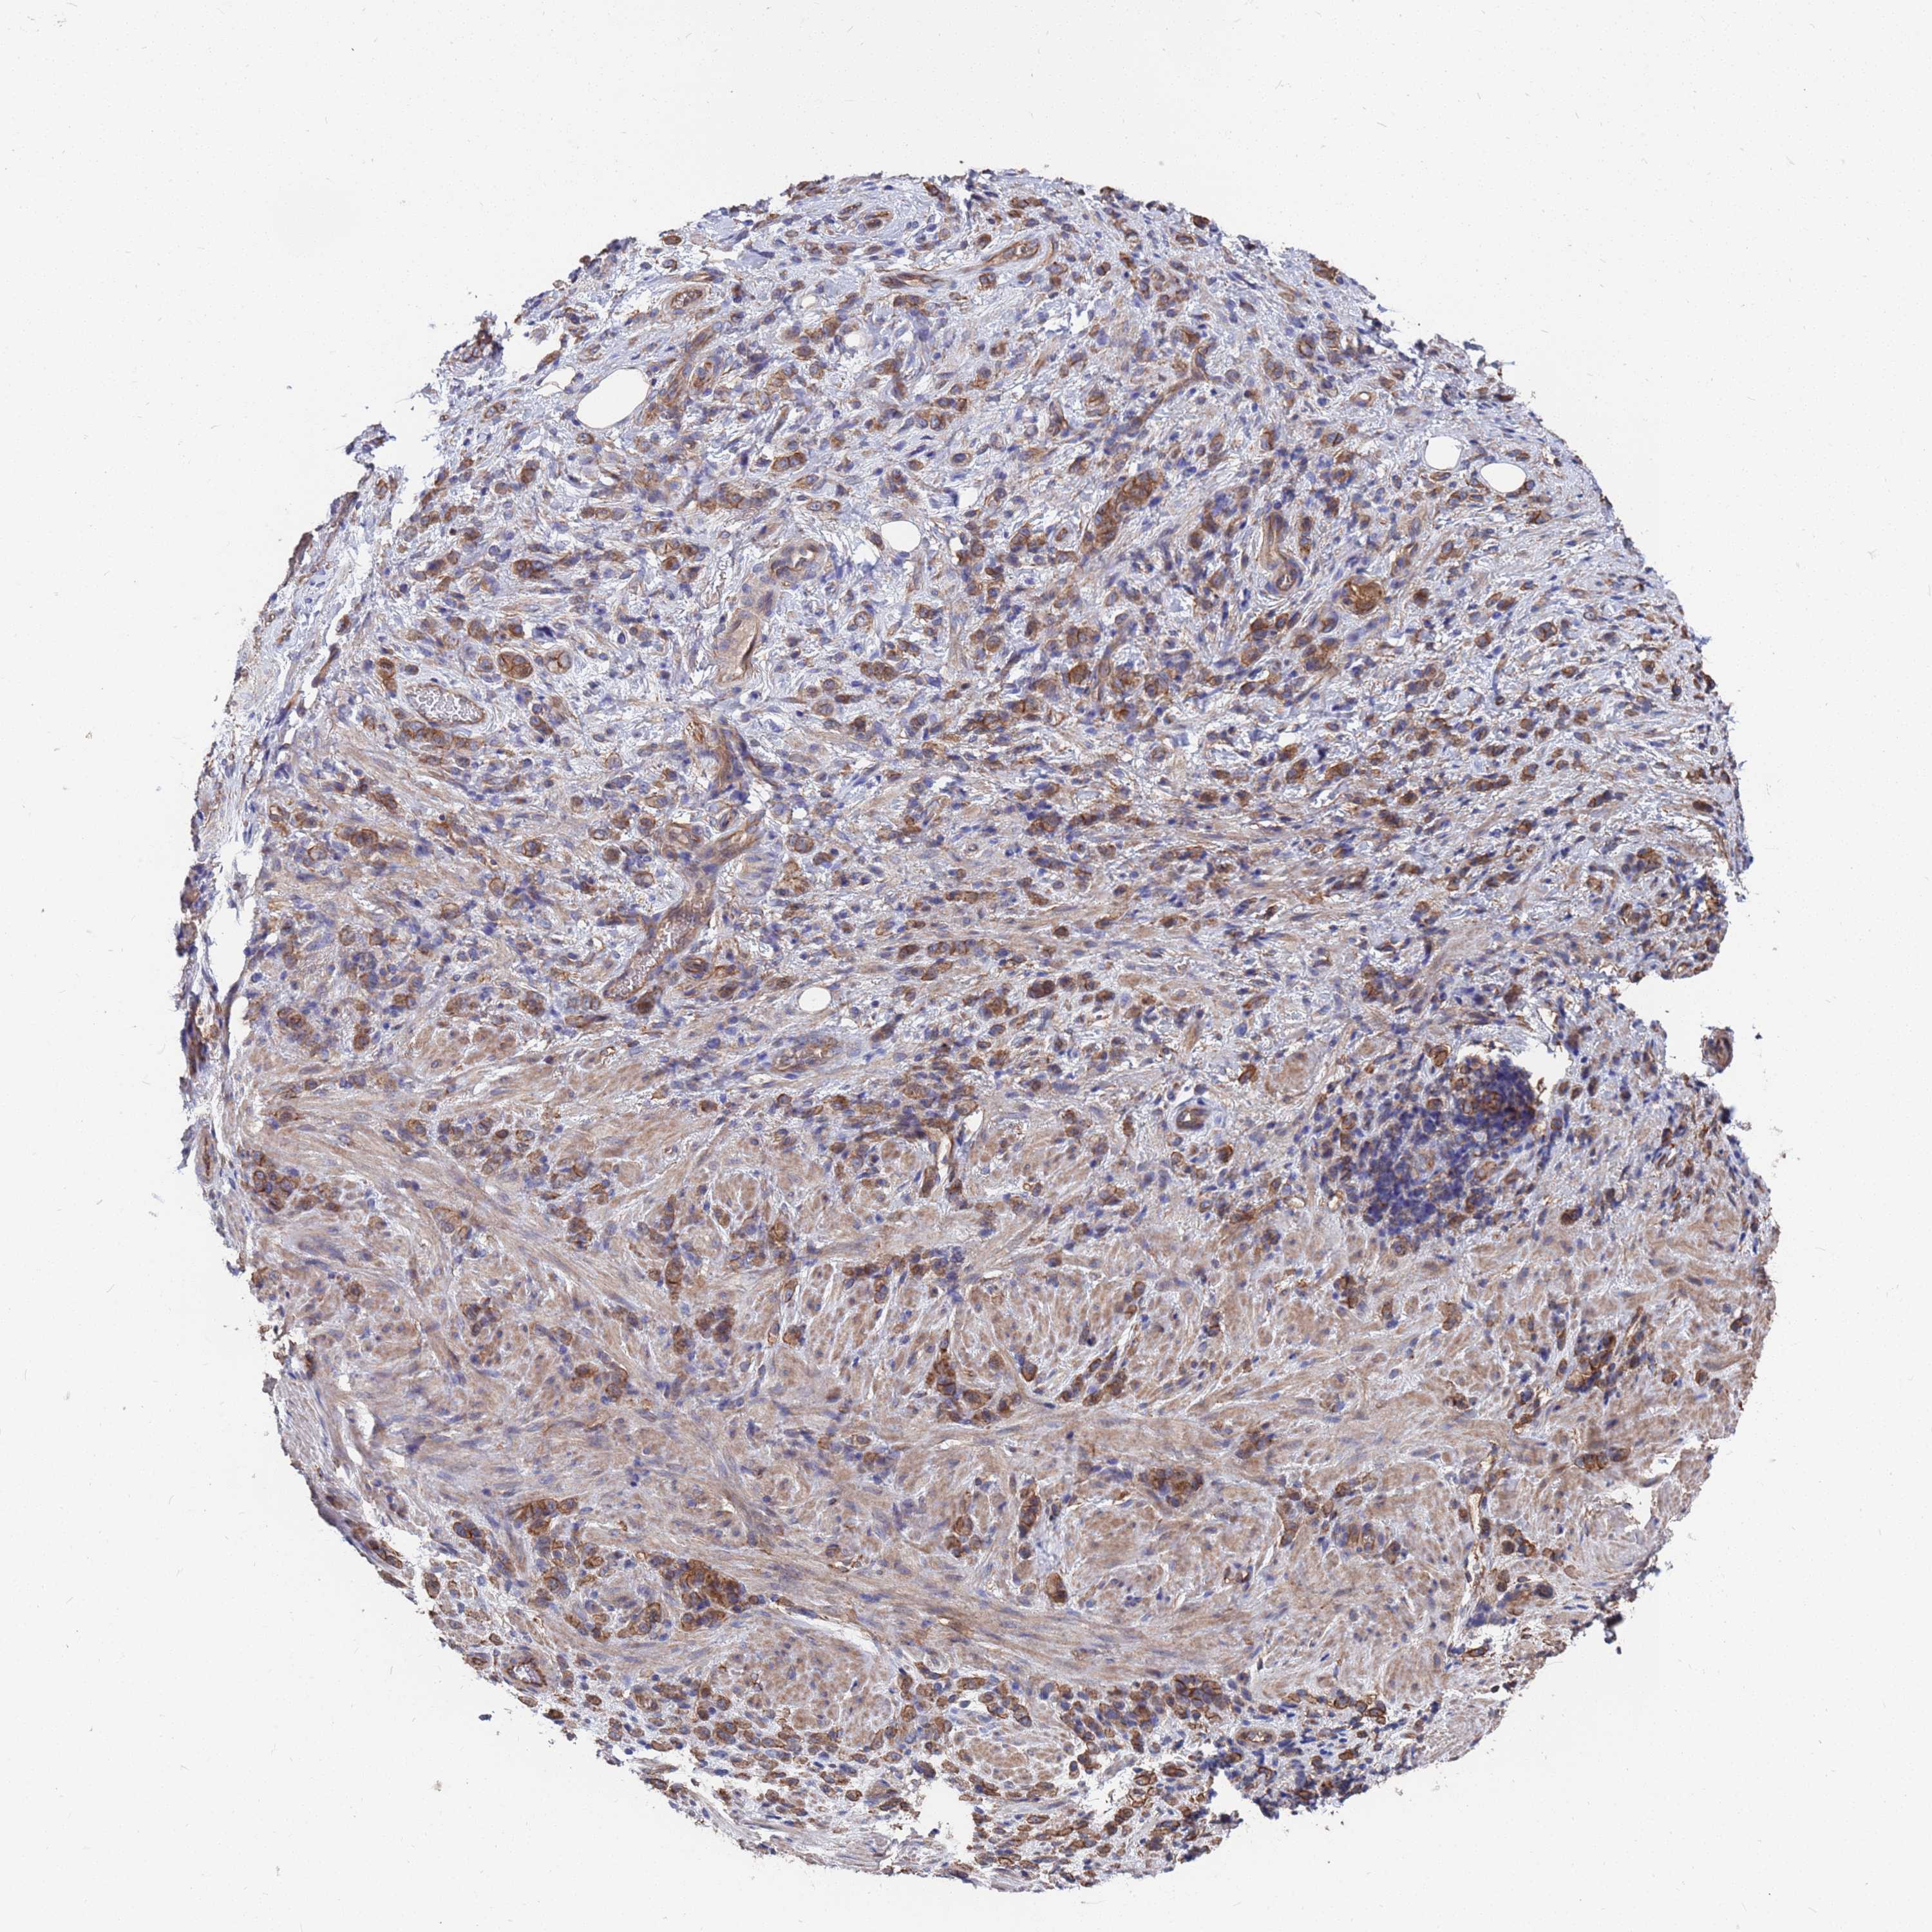

STOMACH CANCER - Protein expressioni

A mouse-over function shows sample information and annotation data. Click on an image to view it in a full screen mode. Samples can be filtered based on level of antibody staining by selecting one or several of the following categories: high, medium, low and not detected. The assay and annotation is described here.

Note that samples used for immunohistochemistry by the Human Protein Atlas do not correspond to samples in the TCGA dataset.

Antibody stainingi

Antibody staining in the annotated cell types in the current human tissue is reported as not detected, low, medium, or high, based on conventional immunohistochemistry profiling in selected tissues. This score is based on the combination of the staining intensity and fraction of stained cells.

Each image is clickable and will lead to virtual microscopy that enables deeper exploration of all samples and also displays staining intensity scores, fraction scores and subcellular localization as well as patient and tissue information for each sample.

Antibody HPA050545

Staining

High

Medium

Low

Not detected

Intensity

Strong

Moderate

Weak

Negative

Quantity

>75%

75%-25%

<25%

None

Location

Nuclear

Cytoplasmic/membranous

Cytoplasmic/membranous,nuclear

Adenocarcinoma, NOS